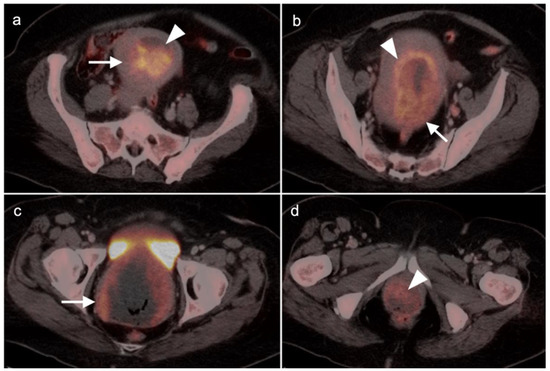

Abstract

2.4. Cervical Cancer

2.5. Vaginal Cancer

2.6. Vulvar Carcinoma